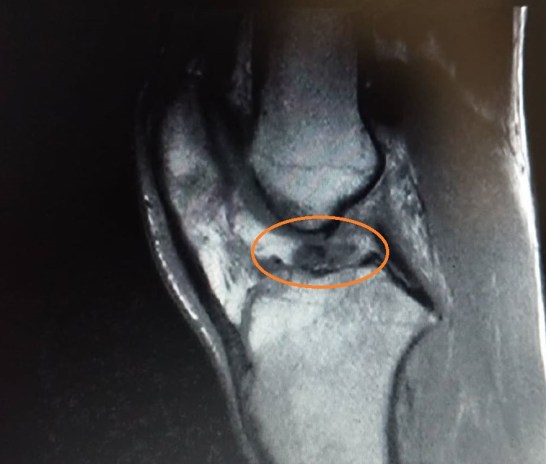

Figura 3: Lesione LCA di grado severo di un ragazzo di 31 anni in RMN

Durante la distorsione del ginocchio puoi sentire in maniera distinta un rumore, il classico “crack”, seguito da un forte dolore e un gonfiore che arriva in brevissimo tempo. In primissima fase può essere utile mettere del ghiaccio (massimo 20 minuti) non tanto per i fini di guarigione, quanto per sentire meno dolore, che si acuirà se l’arto rimane sospeso con il muscolo decontratto (il corpo di solito inibisce il quadricipite in seguito a una distorsione di ginocchio) meno dolore con l’arto in scarico parziale (piede a terra ma con appoggio non completo) quindi sarà utile munirti di stampelle, e tenere l’arto elevato e compresso quando possibile, il ROM (range of motion) del tuo ginocchio sarà limitato sia in estensione che in flessione. Se ti recherai in pronto soccorso l’unico esame che potranno farti sarà una RX per scongiurare fratture, se sarai “fortunato” troverai l’ortopedico che tramite dei test (solitamente cassetto anteriore e Lachman) diagnosticherà la lesione, che verrà poi confermata da una risonanza, da fare solamente quando il ginocchio si sarà sgonfiato, per far sì che le immagini siano chiare.